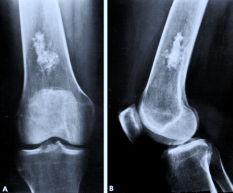

Fibröz Displazi

Fibröz displazi, normal kemik dokusunun yerini proliferatif fibröz dokunun alması ile karakterize kemiğin selim tümörüdür. Kemiğin medullar kanalından kaynaklanır. Görülme yaşı ergenlik çağı ve 20’li yaş grubudur.Monostotik ve poliostotik fibröz displazi olarak iki tipi vardır.Monostotik olanların oranı %70 dir.

Lezyon; kol ve bacak uzun kemiklerinde, kaburgada, leğen kemiğinde ve kafa-yüz kemiklerinde görülebilir. Monostotik fibröz displazi iskelet sistemi gelişmesi esnasında, poliostotik olanlar ise iskelet sistemi geliştikten sonra ortaya çıkar. Poliostotik olanların %2-3’ü endokrin rahatsızlıklarla birliktedir, ciltte sütlü kahverengi lekelerle birlikte çok kemikte lezyon var ise McCune-Albright sendromu denir. İntramusküler miksoma ile birlikte görülürse Mazabraud Sendromu denir.

Kemikte aşırı zayıflık oluşunca patolojik kırık gelişebilir. Uyluk kemiği üst ucunda lezyonun geliştiği fark edilmez ise çoban asası görüntüsü meydana gelir. Düz grafide buzlu cam görüntüsü tipiktir. Genellikle hastaların şikayeti yoktur. Şişlik ve ağrı şikayeti gelişebilir. Fibröz displazi iskelet sisteminin gelişimi ile birlikte büyür. İskelet büyümesi tamamlanınca lezyonun gelişimi yavaşlar.